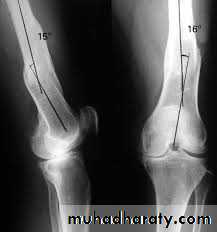

Deformities of the knee joint

In normal adult the knee are in 5-7 degree valgus ; any deviation from this may regarded as deformity .The three common deformities are :

1- bow leg deformity (genu varum) .2- knock knee (genu valgum) .

3- hyper extension(genu recurvatum) .Causes of knee deformities:

Measurement :

: distance between the femoral condyles with the legs held in full extension , and the heel touching ; it should beless than 6 cm .

Knock knee

The distance between the medial malleoli when the knee are held touching; it is usually

less than 8 cm .When the cause of the deformity is physiological .